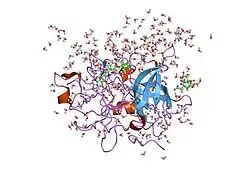

Structure

Urokinase is a 411-residue protein, consisting of three domains: the serine protease domain (consisting of residues 159–411), the kringle domain (consisting of residues 50-131), and the EGF-like domain (consisting of residues 1-49). The kringle domain and the serine protease domain are connected by an interdomain linker or connecting peptide (consisting of residues 132–158). Urokinase is synthesized as a zymogen form (prourokinase or single-chain urokinase), and is activated by proteolytic cleavage between Lys158 and Ile159. The two resulting chains are kept together by a disulfide bond between Cys148 and Cys279.[9]